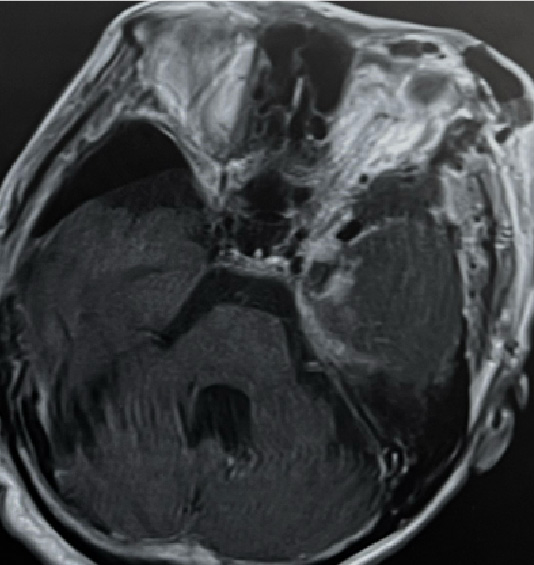

外視鏡と内視鏡を組み合わせて治療した腫瘍のMRI画像です。

髄膜腫:小脳、脳幹、聴神経などが圧迫されている

術前MRI